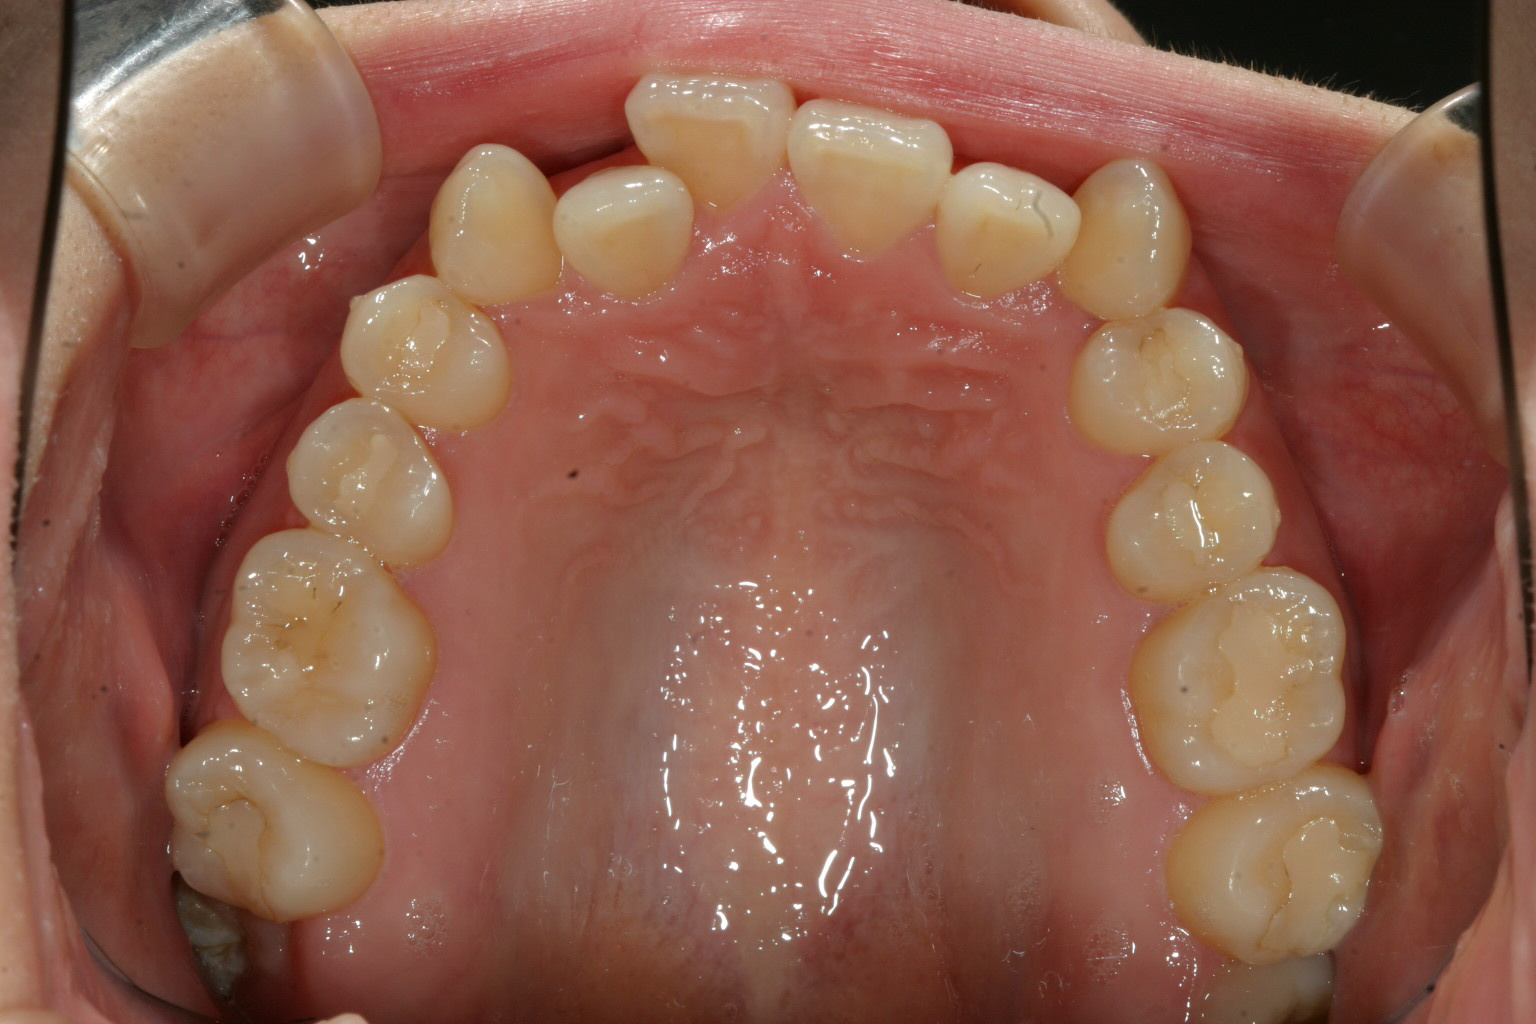

前歯のアーチがガタガタのせいで内方に入ってます。